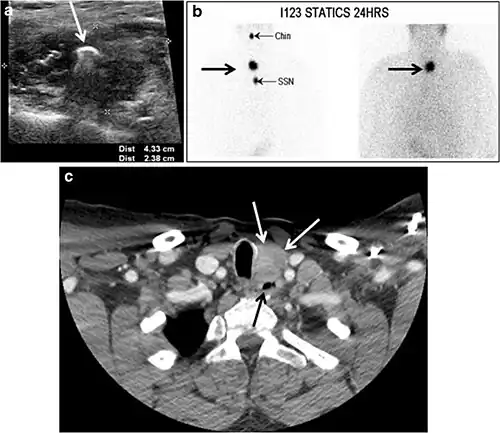

Fig. 17. Ectopic thyroid on the left parotid gland with a palpable left parotid mass in a 69-year-old male patient. a, b Axial and coronal enhanced neck CT scan demonstrates well-defined homogeneous enhancing mass (white arrows) within the left parotid gland with preserved surrounding fat planes. It also shows a normal thyroid in normal position in the lower neck. c Image taken 20 minutes after 5 mCi injected Tc99m-Pertechnetate shows normal thyroid uptake of tracer and physiological uptake in the salivary glands (short black arrow). There is a distinct focus of abnormal tracer accumulation in the left parotid/submandibular region. Patient was given lemon juice with evident normal washout from the salivary glands and relative retention by this abnormal focus (long black arrow).[1] -

Fig. 18. Lingular thyroid in a 33-year-old male who presented with oropharyngeal bleeding. an Axial enhanced neck CT scan at the level of mandible demonstrates a 3 × 3 × 3.4 cm round, partly well-delineated, heterogeneously enhancing lesion (white arrow). It is predominantly on the left side of the oropharynx and to some extent at the mid part of the base of the tongue. The thyroid gland was normal (not shown). b Image of the anterior face and neck taken 20 minutes after Tc99m-Pertechnetate injection shows absent thyroid radiotracer uptake in normal thyroid anatomical location (black short arrows). There is an area of increased uptake (long black arrows) corresponding to the posterior tongue mass identified on CT scan.[1]